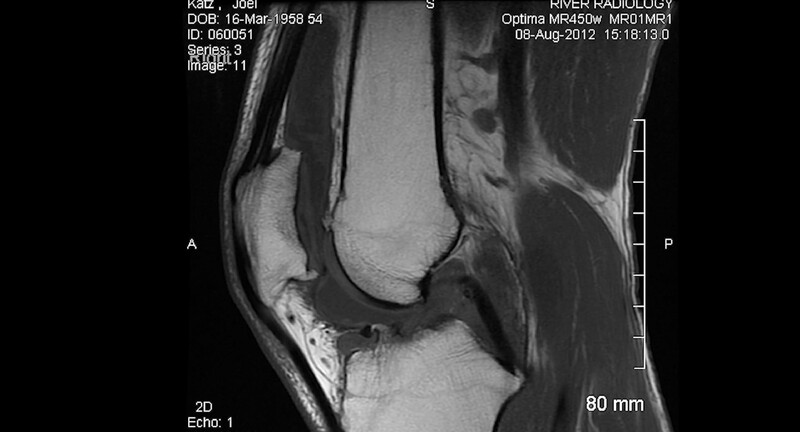

Kneed - Joel Katz

6:00, Digital, B&W Color, 2025

Using X-ray and MRI imagery of the filmmaker's knees taken in preparation for surgery, "Kneed" is an experimental short that explores links between physical and emotional injury.